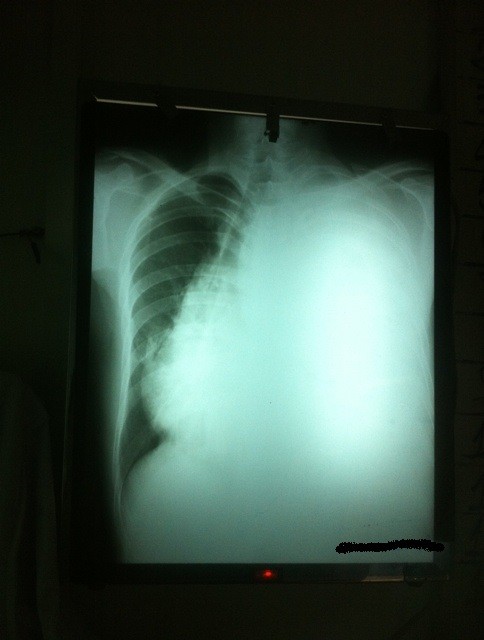

Meanwhile today in my little corner of the world I saw two extraordinary chest x-rays. Both show a whole lung whited out by pleural effusion. This is a rare sight in the First World and would result in each patient being admitted to a high-technology Intensive Care Unit with supported ventilation. Here it is a much more common finding with oxygen administered by nasal prongs the only support available.

Similarly, the left lung here is also completely whited out. The trachea is severely deviated to the right because of the pressure in the left lung and the right lung is much smaller than it should be, as pressure from the left pushes into it, effectively squeezing it.

Both of these men presented today with extreme breathlessness and very poor respiratory clinical findings. Both are at risk of death if the cause is not diagnosed and treated.